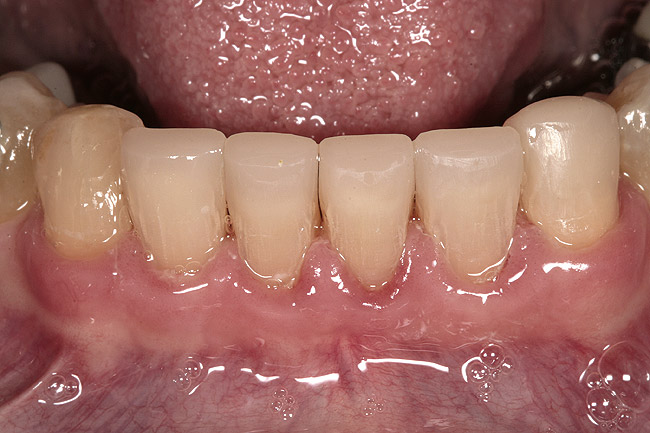

Figure 4  The brackets are removed and the teeth direct-bonded to a pleasing length.

Figure 4

Again, the starting point is a set of mounted models, an orthodontic set-up, and a diagnostic wax-up. The worn teeth are cut from the set-up and waxed to normal length. They are then replaced in the set-up and become the guide for treatment. Whether they are lengthened before or during orthodontics depends upon whether space exists to lengthen them prior to orthodontics. If it does, they can be temporarily restored prior to treatment. If not, the orthodontist must first create space, then de-bracket the worn teeth and send the patient to the restorative dentist for temporary restoration. The brackets are then replaced and the orthodontics completed. The need to open space prior to correcting tooth length is common when utilizing orthodontics to intrude severely worn and over-erupted maxillary or mandibular incisors (Figure 2, Figure 3, Figure 4 and Figure 5).